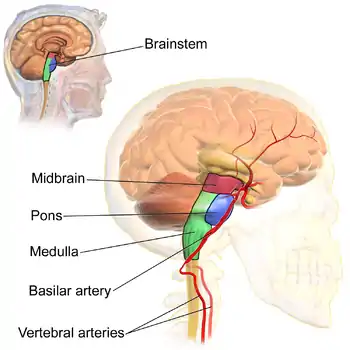

The three distinct parts of the brainstem are colored in this sagittal section of a human brain. | |

The brainstem (or brain stem) is the stalk-like[1]: 152 part of the brain that interconnects the cerebrum and diencephalon with the spinal cord.[2] In the human brain, the brainstem is composed of the midbrain, the pons, and the medulla oblongata.[3][1]: 152 The midbrain is continuous with the thalamus of the diencephalon through the tentorial notch.[1]: 152

The parts of the brainstem are the midbrain, the pons, and the medulla oblongata; the diencephalon is sometimes considered part of the brainstem.[7]: 248

Pons

The medulla oblongata, often just referred to as the medulla, is the lower half of the brainstem continuous with the spinal cord. Its upper part is continuous with the pons.[7]: 1121 The medulla contains the cardiac, dorsal and ventral respiratory groups, and vasomotor centres, dealing with heart rate, breathing and blood pressure. Another important medullary structure is the area postrema whose functions include the control of vomiting.

Blood supply

The main supply of blood to the brainstem is provided by the basilar arteries and the vertebral arteries.[11]: 740